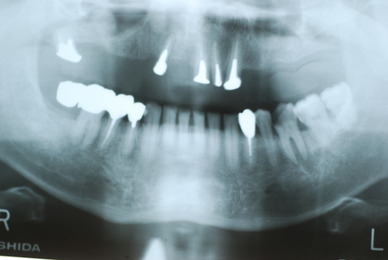

²¼³Ü²£¸þ¤¤Î¿ÆÉÔÃΤòºòÆüÈ´»õ¤·¤¿Êý¤ÎËÜÆü¤Î¾õÂ֤Ǥ¹¡£

°ì±þÌô¡Ê¾Ã±êÄÃÄ˺ޡˤò½Ð¤·¤Æ¤¤¤Þ¤·¤¿¤¬¡¢°ìγ¤â»ÈÍѤ·¤Æ¤¤¤Þ¤»¤ó¡£

Äˤߤâ¼ð¤ì¤â¤Ê¤¤¾õÂ֤Ǥ¹¡£Ë¥¤Ã¤Æ¤¤¤Ê¤¤¤Î¤ÇÈ´¤¤¤¿½ê¤ÏϪ½Ð¤·¤Æ¤¤¤Þ¤¹¡£¤À¤«¤é¤³¤½¼ð¤ì¤Ê¤¤¤Î¤Ç¤¹¤Í¡£Ë¥¹ç¤¹¤ë¤ÈÆâ½Ð·ì¤·¤Æ¼ð¤ì¤ë¤Î¤Ç¤¹¡£

»Äǰ¤Ê¤³¤È¤Ë½ý¸ý¤Ï³«¤¤¤Æ¤¤¤Þ¤·¤¿¡£